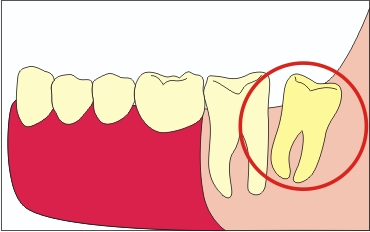

A disztális meredeksége a csoport nyolc

Ez a dőlés felé az arcon vagy a nyelv, ami ahhoz vezethet, hogy a nyálkahártya sérülése a krylochelyustnoy redők és okoz a krónikus sérülések arcon vagy nyelv.